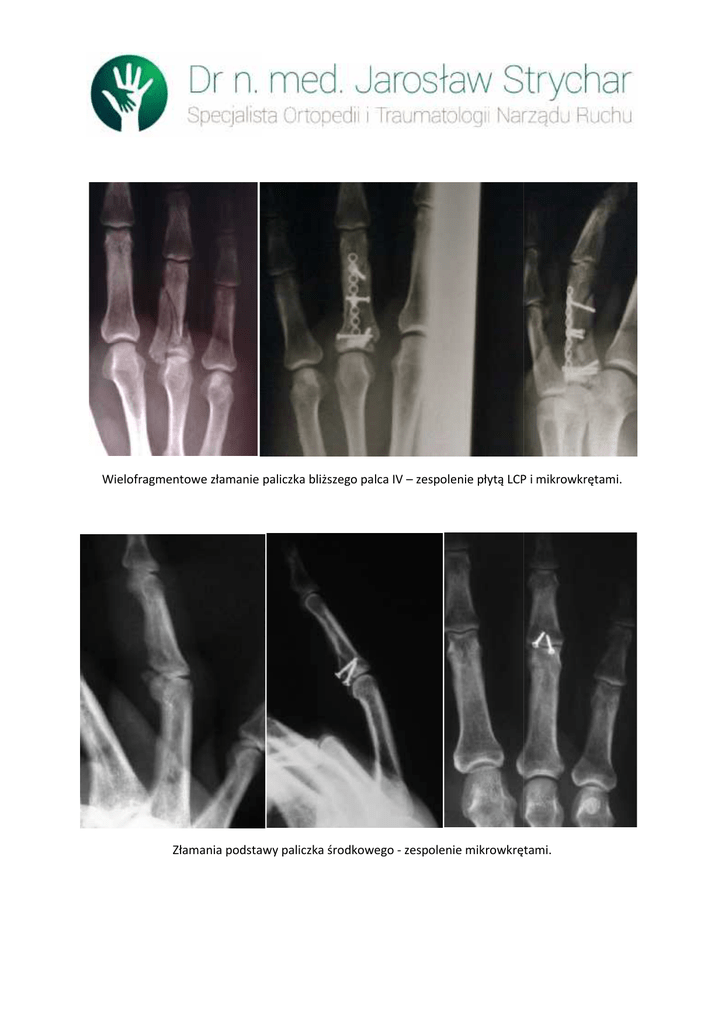

Wielofragmentowe złamanie paliczka bliższego palca IV – zespolenie płytą LCP i mikrowkrętami.